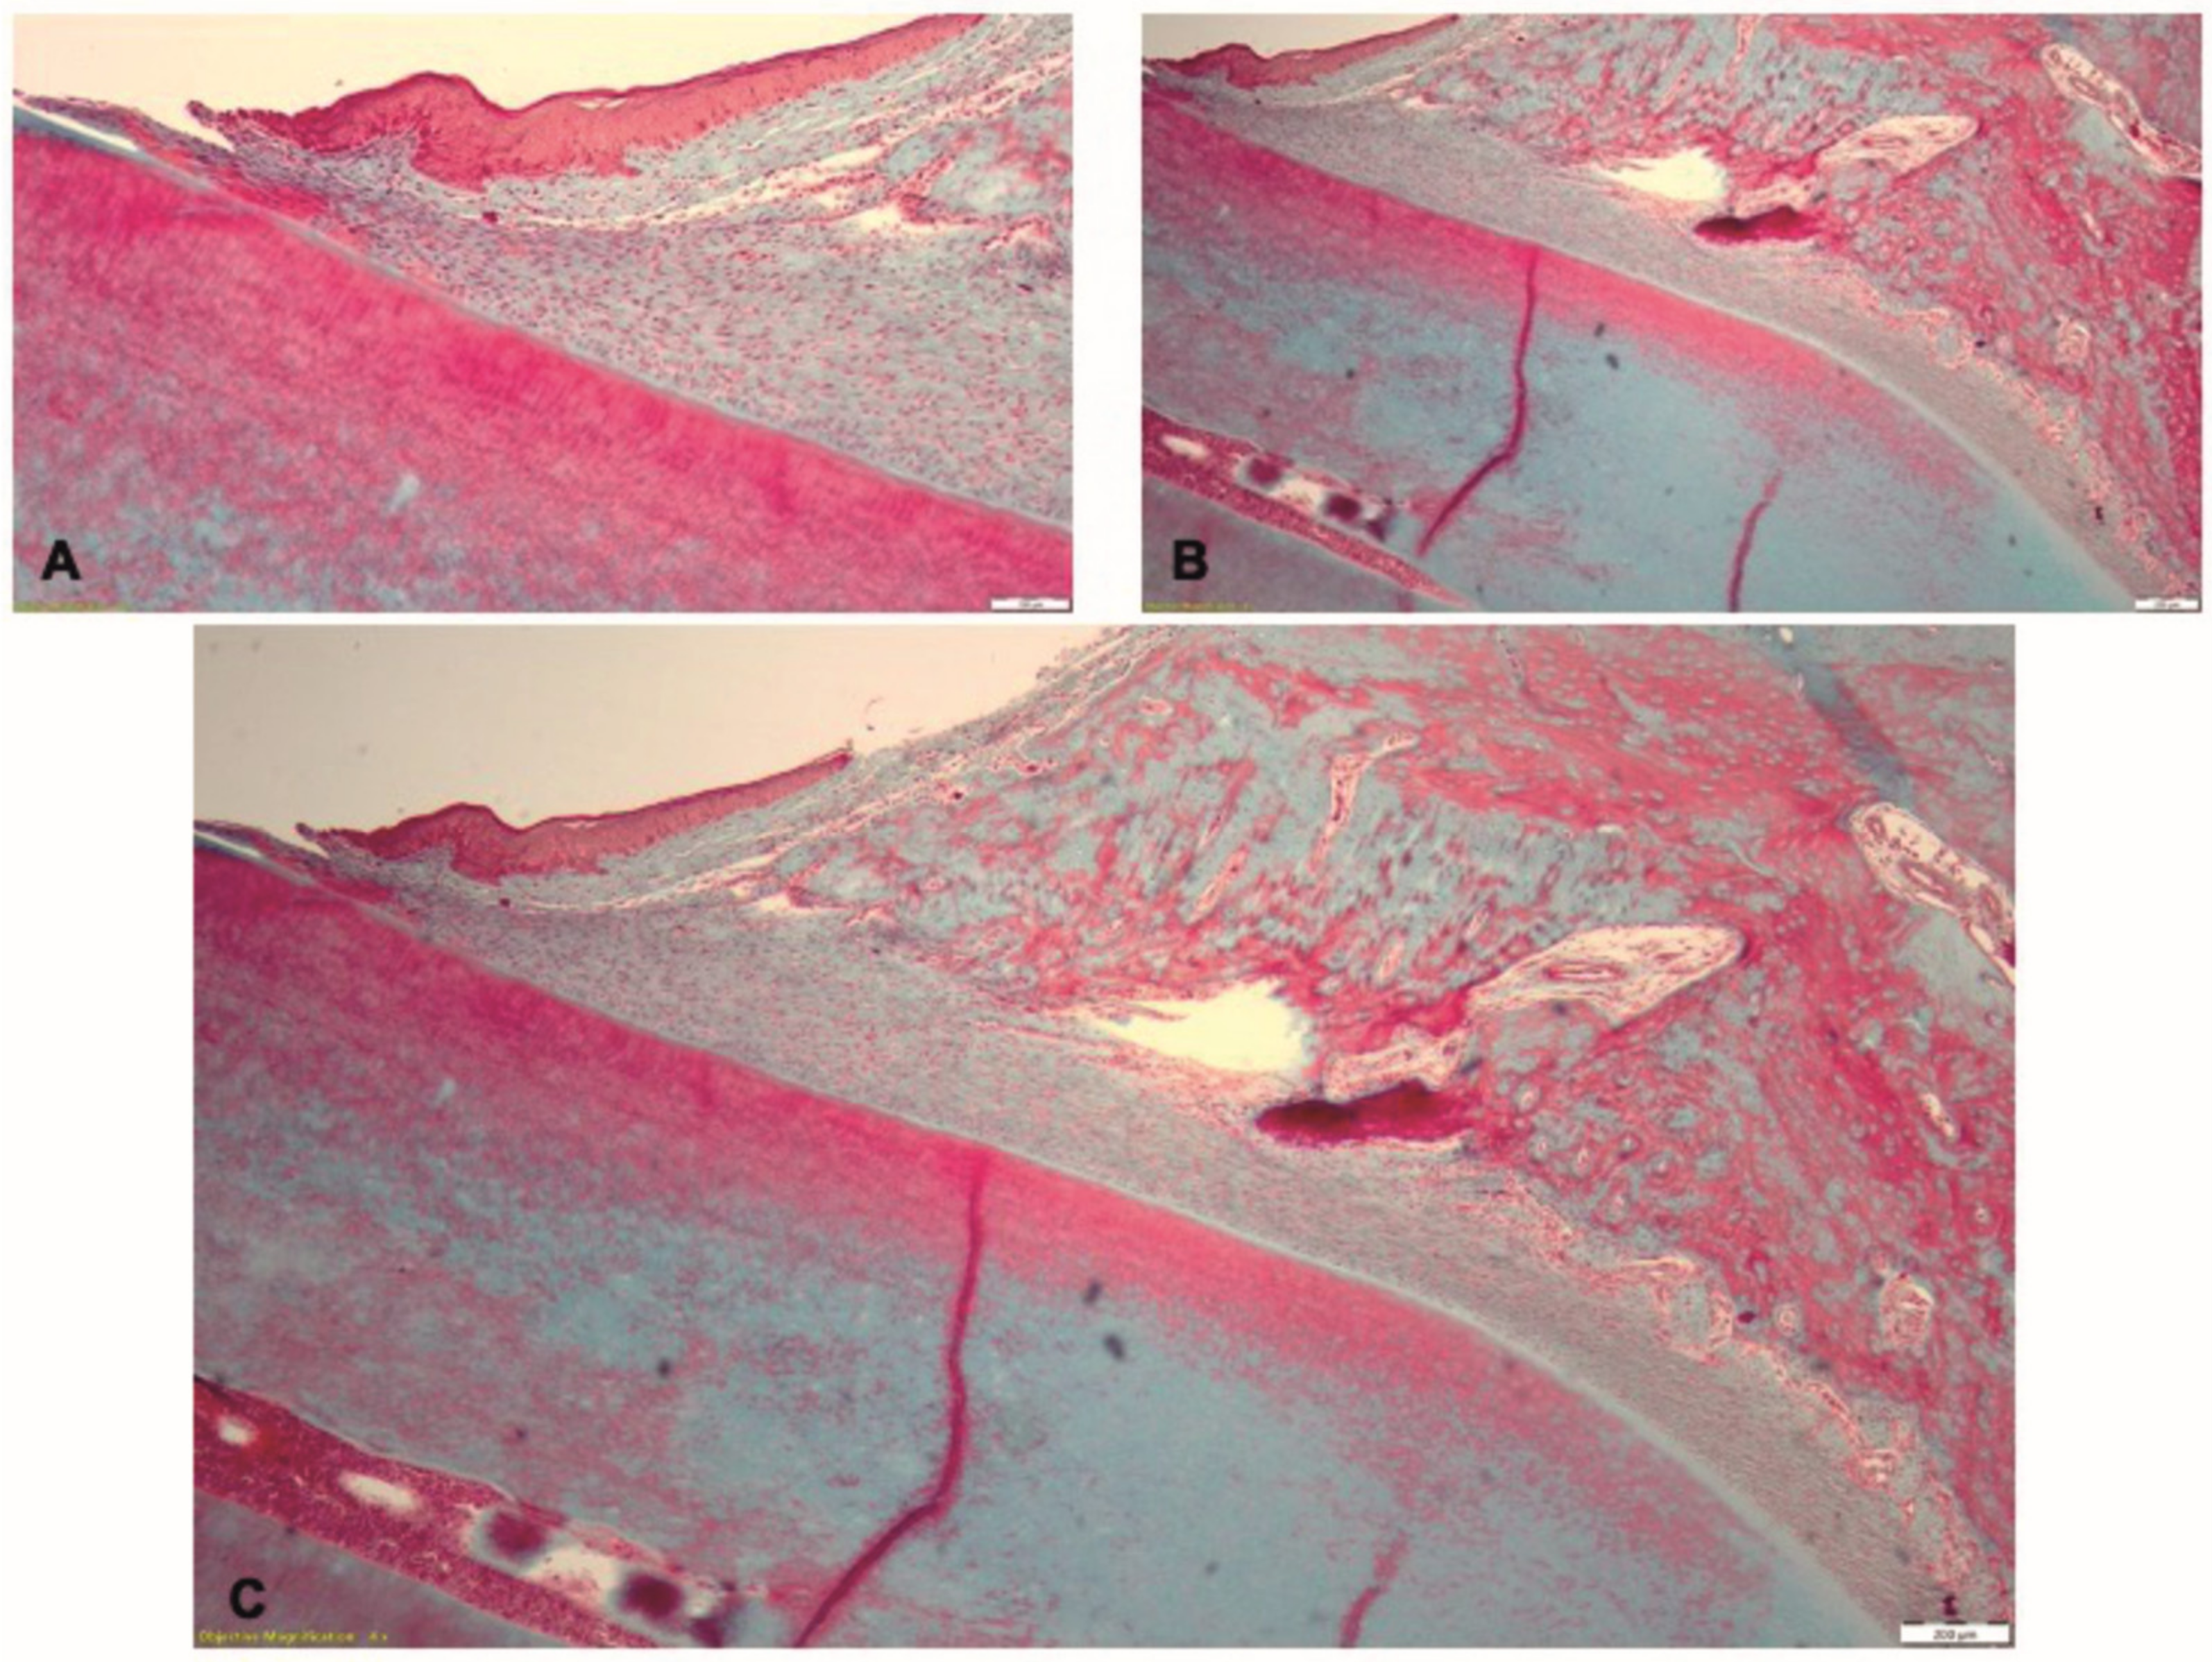

In Phase 3, in the T1 group, the gingival epithelium exhibited partial healing: in some limited zones, the epithelium was thinner, whereas in other zones the epithelium had normal structure. In the gingival lamina propria, the zones of inflammatory infiltrate were associated with the altered epithelium (Figure 11A). In the coronal part of the periodontal ligament and adjacent to the alveolar crest, the inflammatory infiltrate consisted of polymorphonuclear neutrophils, macrophages with vacuolated cytoplasm, lymphocytes, plasma cells and several multinucleated cells (Figure 11B). The alveolar crest shows resorption on isolated areas. In the profound zone of the periodontal ligament, discrete inflammatory infiltrate with few neutrophil, lymphocytes and plasma cells could be seen (Figure 11C).

In Phase 3, in T2 group, the histological examination indicates healing of the gingival epithelium (Figure 12A). Few isolated infiltrates with neutrophils and lymphocytes were seen in the lamina propria and the periodontal ligament (Figure 12B). The alveolar bone had normal aspect and the periodontal ligaments inserted on the bone (Figure 12C).

The histological examination confirmed, in Phase 2, the experimentally-induced periodontal inflammation and revealed the features associated with the different therapeutic approaches in Phase 3. After treatment, the histological aspect of tissue healing in the T1 group was consistent with the clinical parameters. In the periodontal tissues, no nanofiber residue could be seen, suggesting the possibility of complete resorption of the biomaterial. However, a complete resorption of the applied material cannot be concluded, as no chemical identification test was conducted for PLA, nano-HAP or doxy. PLA is known to be biocompatible, but during the resorption process, a chronic inflammatory infiltrate could be seen at the implant site. The persistence of the focal chronic inflammation in the gingival lamina propria and adjacent to the alveolar crest, and the resorption of the alveolar bone were due to the trauma caused by the application of the nanofiber implant. In order to support of the periodontal tissues and to achieve the local concentration of doxy necessary for the therapeutic effect, the size of the matrix samples was predetermined. The physical properties of the biomaterial enabled the condensation of the matrix sample in the periodontal pocket, but due to the excessive size of the matrix and the increased pressure during application, the periodontal tissues were injured. Moreover, the particular physiology of the continuous eruption of the murine incisors and the short period of time between the application of the biomaterial and the histological examination could also explain the incomplete healing of the periodontal tissues. In the T2 group, the non-surgical treatment promoted the periodontal healing through the activation of natural mechanisms; thus, the normal histological aspect of the periodontal tissues could be identified.

Figure 11. Histological aspect of the T1 group in Phase 3, after treatment with the novel biomaterial: (A) the gingival epithelium showing partial healing; (B) chronic inflammatory infiltrate in the lamina propria and in the proximity of the alveolar crest; (C) persistence of isolated zones of inflammation in the periodontal tissues; Goldner’s trichrome staining.

Figure 12. Histological aspect of the T2 group in Phase 3, after treatment by mechanical debridement: (A) the gingival epithelium with normal structure; (B) isolated zones of inflammatory infiltrate in the gingiva and the periodontal ligament; (C) periodontal ligament fibers inserted on the alveolar bone; Goldner’s trichrome staining.